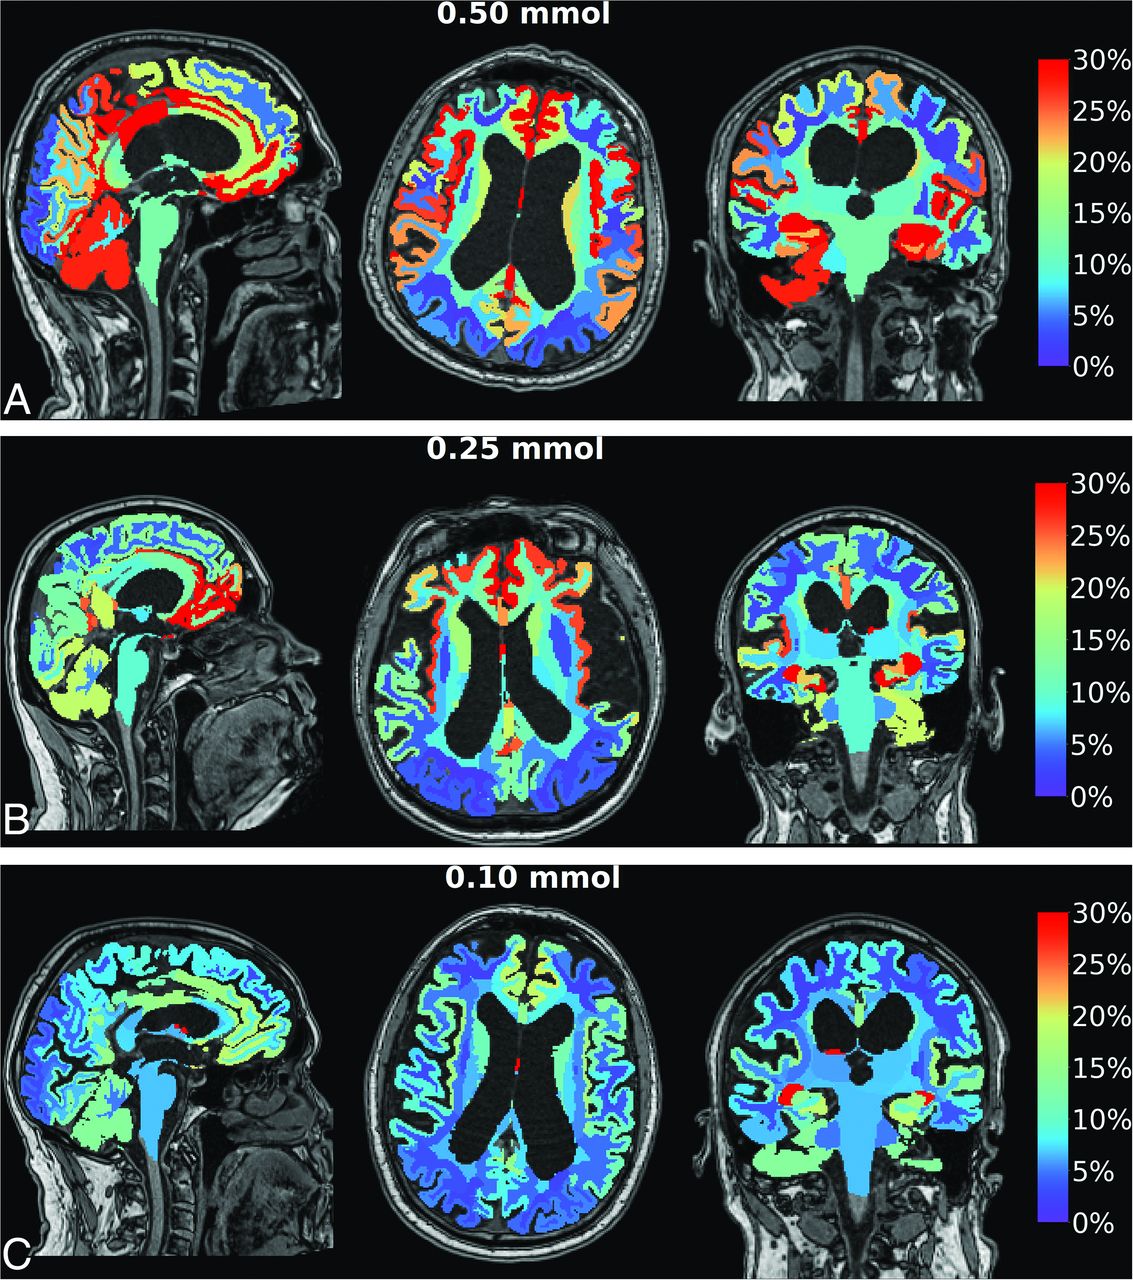

Contrast enrichment in the cranial CSF spaces was verified in all patients by observation of any T1 signal enhancement in the cranial CSF spaces on MR imaging. Figure 1 shows contrast enrichment in the brain after 24 hours in patients with iNPH, depending on the dose of intrathecal gadobutrol, visualized by 1.5T MR imaging. The contrast enhancement in the ventricles is shown in Fig 2.

Enrichment in the ventricles by gadobutrol, used as a CSF tracer, in patients with iNPH. Axial, sagittal, and coronal MR imaging visualizes dose-dependent ventricular tracer enrichment 24 hours after intrathecal gadobutrol in the iNPH cohort examined with 1.5T MR imaging at the group level in which intrathecal gadobutrol was given in the doses of 0.50 mmol (n = 19) (A), 0.25 mmol (n = 68) (B), and 0.10 mmol (n = 26) (C) . The percentage change in normalized T1 signal at 24 hours is shown on the color bar. Here, CSF tracer in the brain is removed, showing CSF tracer enrichment of the cerebral ventricles. The high degree of ventricular CSF tracer enrichment is due to the high proportion of patients with iNPH in the study, in whom ventricular reflux of CSF tracer is typical.10

Accumulating evidence indicates the benefits of administering GBCA intrathecally. For years, clinicians have used intrathecal GBCA for visualization of CSF leakage in individuals with spontaneous intracranial hypotension.15,16 In our clinical practice, we have also used gMRI for the diagnostic assessment of ventricular reflux (Fig 2) and for estimation of impaired molecular clearance from intracranial CSF spaces and the brain (Fig 1). Hence, we have reported its utility in iNPH,10 idiopathic intracranial hypertension,17 and chronic sleep disturbance.18 Currently, we consider intrathecal contrast-enhanced MR imaging the criterion standard for imaging of glymphatic function, providing information not obtained by other imaging modalities. In a previous study, we showed that intrathecal gadobutrol in a dose of 0.25 mmol (but not 0.10 mmol) is sufficient for gMRI in iNPH using a 1.5T MR imaging scanner.11 When intrathecal gadobutrol is given for the assessment of CSF-to-blood clearance capacity, a dose of 0.10 mmol is sufficient.19